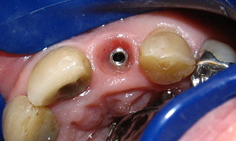

A.2. Absence of soft tissue. Delaying implant placement10 or performing soft tissue grafts and the placement simultaneously is recommended. It is currently believed that an adequate amount of soft tissue helps prevent marginal recession, hide the margins of the restoration and disguise the shadow in the implant platform11,12 (Figs. 1, 2). Moreover, from an aesthetic perspective, an adequate amount of keratinized tissue is crucial as it allows for a harmonious gingival contour without inflammation, light pink and spotted, synonymous with pink aesthetics. It is therefore impossible to achieve adequate aesthetic outcomes in the aesthetic area without the right amount of keratinized tissue.

B.1. Correct implant selection. Aesthetic failures can occur when selecting an inappropriate implant, mainly as a consequence of using large diameter implants. The implant selected must not come into contact with the vestibular table in order to leave a gap between them, in anticipation of the dimensional changes in the socket after extraction8 (Figs. 3, 4). Evans and Chen (2008) 13 found that contact between the implant shoulder and the vestibular table was a significant factor in gingival recession. This proximity to the vestibular table can be due either to incorrect implant placement or to the fact that the diameter was incorrectly selected. Selecting the diameter of the implant based solely on the dimensions of the tooth to be replaced, or using implants with enlarged platforms or wide-neck implants, must be avoided. In these cases, the implant shoulder can be too close to the vestibular bone and adjacent teeth, considerably increasing the risk of recession2 (Fig. 5).

B.3. Implant design. Platform switching implants, that is, implants with a connection in which the diameter of the abutment is smaller than the diameter of the implant, are recommended for the aesthetic area. The gap is therefore moved toward the center of the implant, which reduces crestal bone resorption and allows for an increased growth of soft tissue14,16,17 (Fig. 7).

-Shape. The shape of the abutment is one of the factors to consider. Using straight abutments or abutments with diameters smaller than the implant platform is advisable to preserve as much peri-implant soft tissue as possible. Authors such as Zuhr35 recommend a subcontoured abutment, which favors the adaptation of gingival tissues during healing and prevents gingival recession due to excessive compression (Fig. 10).

-Platform. Another aspect to consider to preserve the bone crest is platform switching, in which the diameter of the abutment is smaller than the implant platform. Thus, the implant-abutment microgap is horizontally relocated, which creates a healthy biological width.